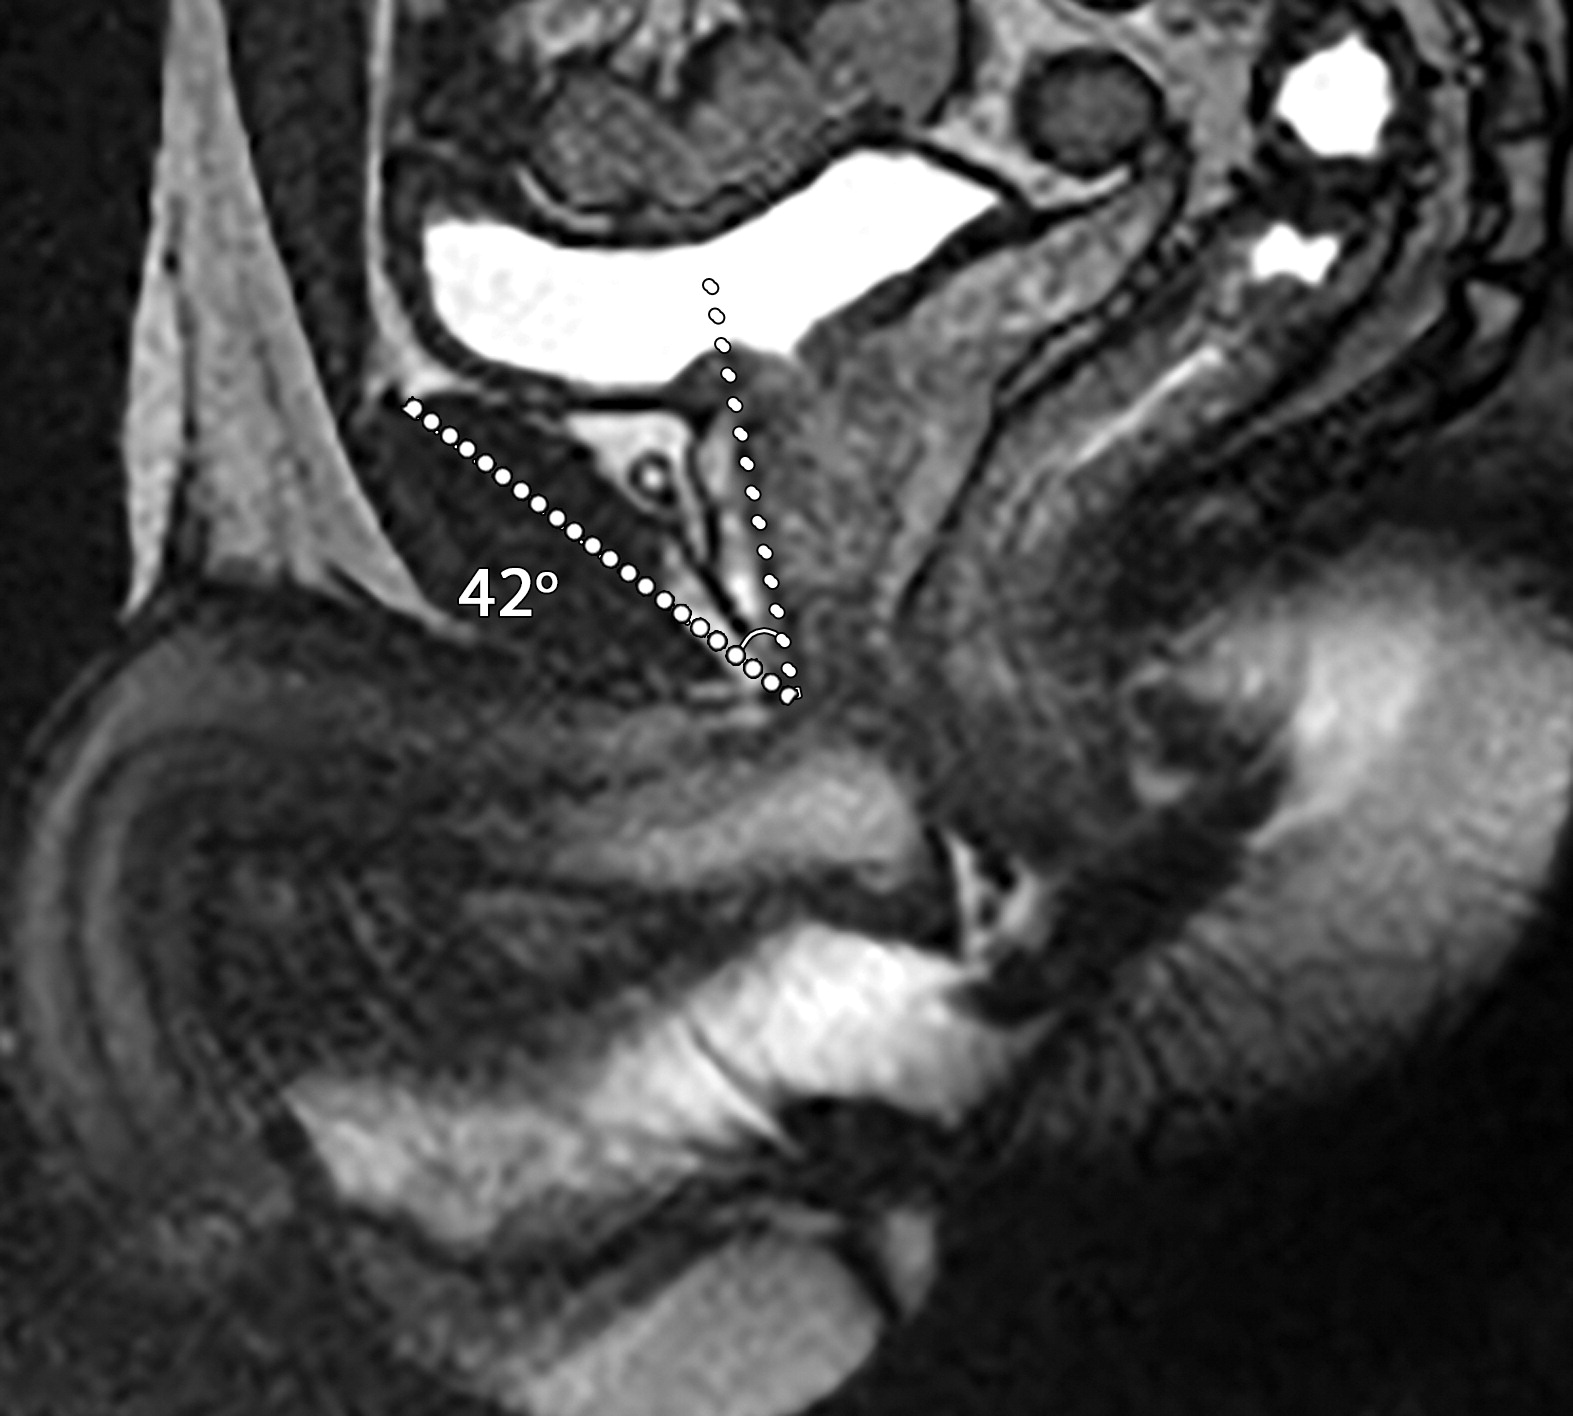

耻骨前列腺和前列腺尿道角

患者男性,39岁,良性前列腺增生,骶正中线TrueFISP MR图像显示,耻骨前列腺角从静息时的42°(a)正常增加到用力时的91°(b)。(c)67岁男性的矢状位T2加权MR图像显示前列腺-尿道角测量值为66°。